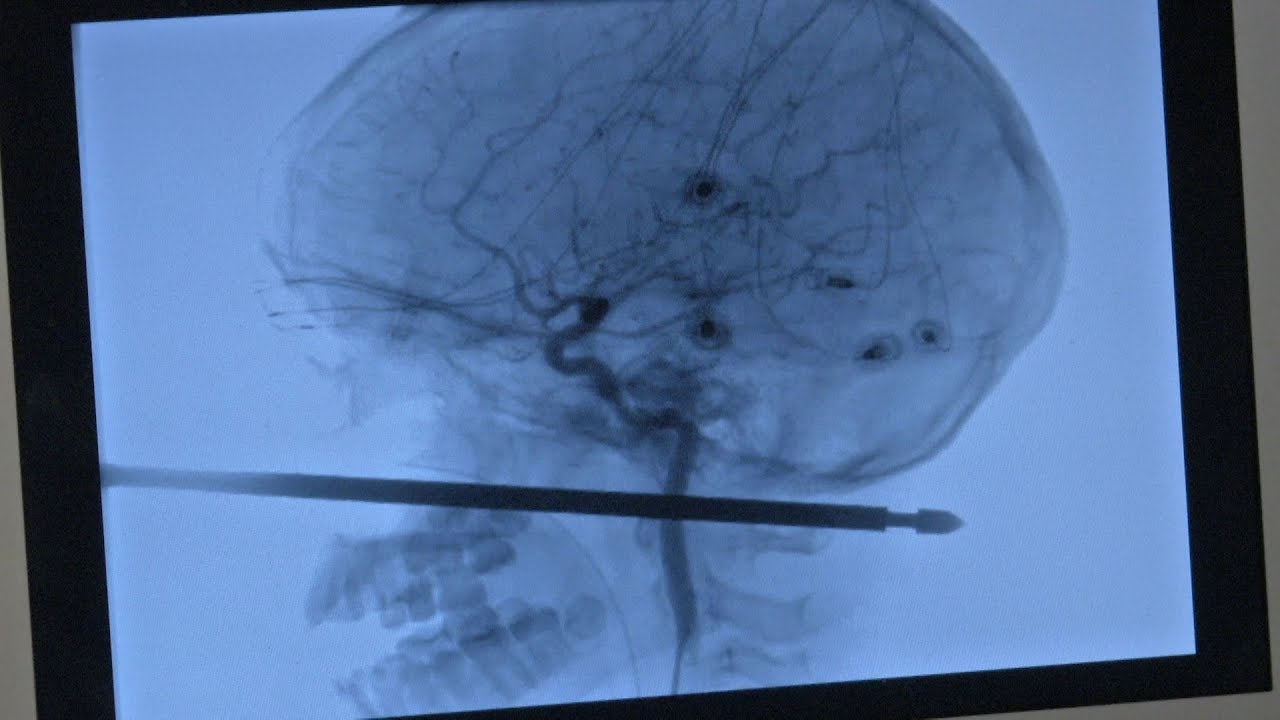

“This thing had spared the eye, spared the brain, spared the spinal cord,” Koji Ebersole, director of endovascular neurosurgery at The University of Kansas Health System, told the Star. “But the major concern was the blood vessels in the neck.”

Scans showed that the spike had missed major vessels. “You couldn’t draw it up any better,” said Ebersole. “It was one in a million for it to pass 5 or 6 inches through the front of the face to the back and not have hit these things.”

Here’s a video of Ebersole discussing the operation: